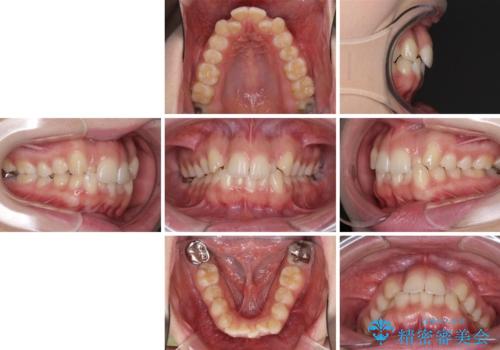

- 前歯のデコボコと八重歯を気にして来院された患者様です。

叢生の程度は中等度であったため、IPR(歯と歯の間を削る)と歯列の側方拡大をメインに、インビザラインを用いて歯列を改善することとしました。

また、下顎骨の右側変位による右側臼歯の咬合を改善させるよう試みることとしました。

右側の咬合改善を目標に様々な手法を用いましたが、骨格的なズレによる不正咬合はインビザラインでは改善することができませんでした。